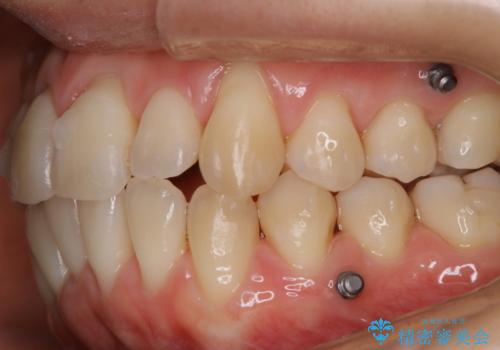

- インビザラインでの矯正治療中ですが、結婚式があるため全体の着色・ステインを綺麗にしたいとのことでした。PMTC60分コースを行いました。

PMTC(保険外治療)は、毎日の歯磨きで落としきれない汚れや、コーヒ、紅茶・タバコのヤニなどの着色も除去します。目には見えない歯と歯の間・歯肉の境目・インビザライン中はアタッチメント周囲などに残っているプラーク(歯垢)もしっかり取り除きます。PMTCでは専門的な機械や材料を使用して、徹底的に汚れを除去するため、虫歯・歯周病・口臭予防などにつながります。